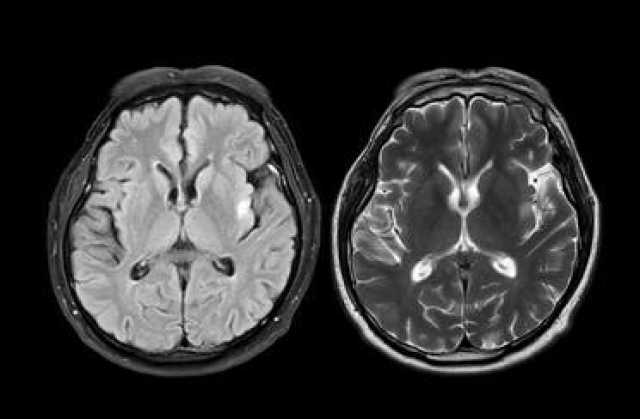

ويحدث المرض بسبب موت الخلايا العصبية المنتجة لمادة الدوبامين، وهي الناقل الكيميائي المسؤول عن التحكم في الحركة. وتبدأ الأعراض عادة ببطء شديد وتشمل الرعشة، وبطء الحركة، وتصلب العضلات، وفقدان التوازن، إلى جانب أعراض غير حركية مثل الاكتئاب، واضطرابات النوم، وفقدان حاسة الشم.

لكن التحدي الأكبر هو أن الأعراض لا تظهر إلا بعد فقدان نحو 60 إلى 70% من الخلايا العصبية المسؤولة عن الحركة، ما يجعل التشخيص في كثير من الأحيان متأخرًا جدًا لبدء العلاج الفعّال.